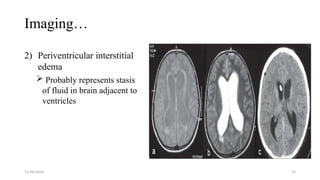

Imaging…

2) Periventricular interstitial

edema

 Probably represents stasis

of fluid in brain adjacent to

ventricles